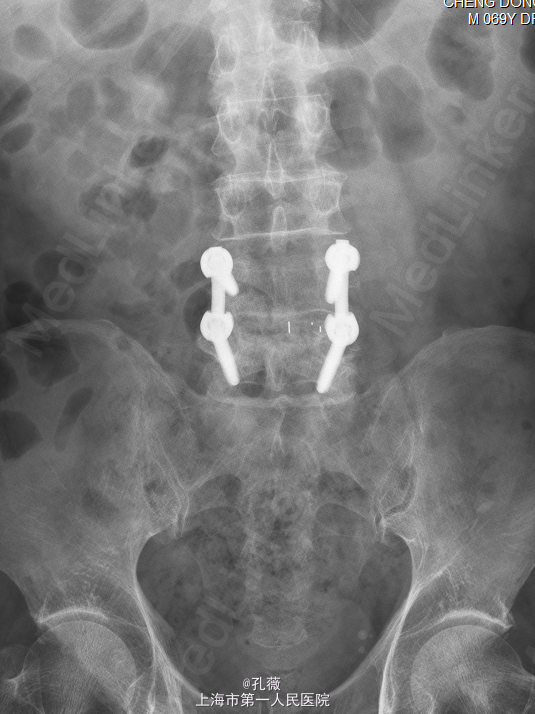

患者,男,69岁,因“腰痛伴行走活动受限10余年”入院。 患者诉40余年前有外伤致腰4椎峡部裂住院病史,后未感明显的腰部不适合疼痛。10余年前无明显诱因下出现腰痛,两侧椎旁腰骶部感觉酸胀痛,渐渐加重,行走活动受限,休息卧床时疼痛减轻,行走后加重,现患者感站立时腰痛明显,伴有右足部第1.2趾背部麻木。

脊椎外观无畸形,腰4、5棘突及双侧椎旁压痛、叩击痛(++),双下肢直腿抬高试验阴性.当地医院腰椎X线和CT提示:“腰椎退行性变,腰4椎体椎弓峡部裂伴向前滑移。”

初步诊断: 腰4椎体峡部裂,腰4椎体滑移. 处理: 行全麻下腰椎后路减压植骨融合内固定术。

术后予以补液支持治疗,密切观察患者肢体血供及感觉情况。